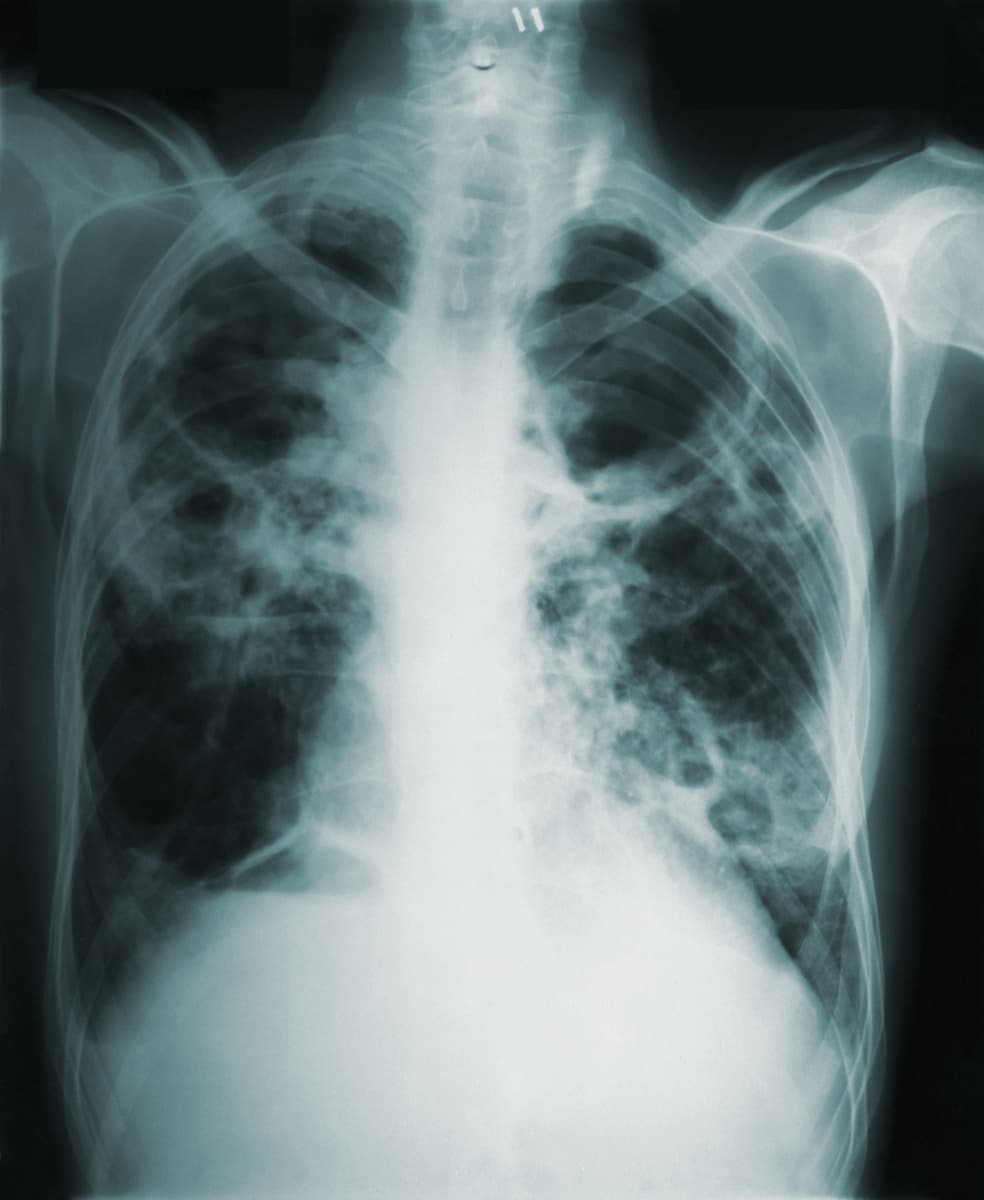

Tuberculose diminui durante pandemia mas por subnotificação e atrasos no diagnóstico

Estamos melhor ou pior do que antes da pandemia?